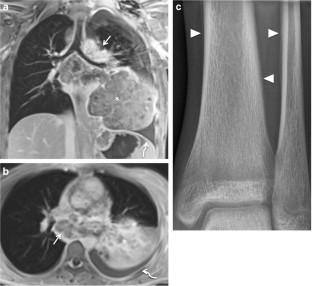

Fig. 4